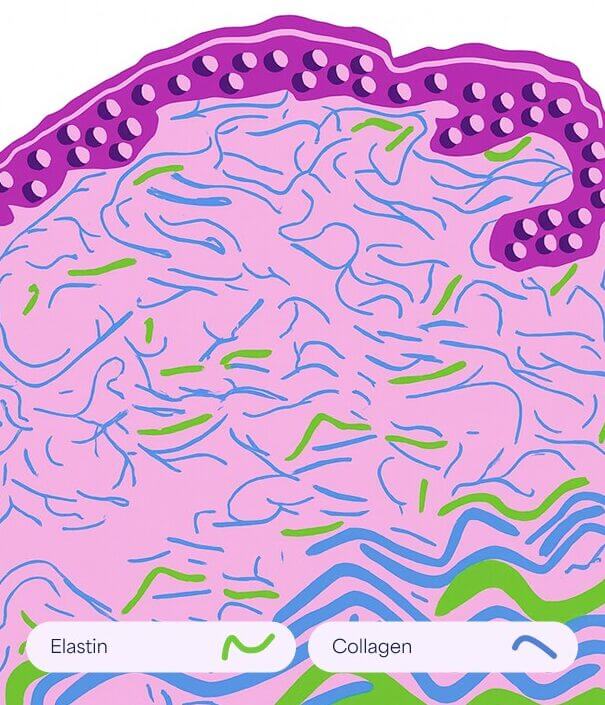

This aging process is accompanied by structural and functional changes in extracellular matrix components such as collagen and elastin. The result in the appearance of fine lines and wrinkles.

How it works

- Promotes removal of old damaged collagen

- Induces keratinocytes proliferation that releases growth factors to promote collagen deposition by the fibroblasts and elastin deposition

- Modulates the expression of several genes in the skin (vascular endothelial growth factor, fibroblast growth factor, epidermal growth factor, collagen type I and III) that promote extracellular matrix remodeling

Enlarged pores are visible surface irregularities caused by high sebum production, reduced elasticity, increased follicle size, and factors like acne, hormones, and skincare habits.

How it works

Promotes removal of old damaged collagen

Induces keratinocytes proliferation that releases growth factors to promote collagen deposition by the fibroblasts and elastin deposition

Modulates the expression of several genes in the skin (vascular endothelial growth factor, fibroblast growth factor, epidermal growth factor, collagen type I and III) that promote extracellular matrix remodeling